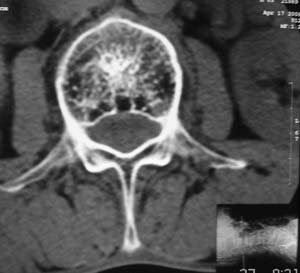

以下是引用余辉在2008-4-27 17:12:00的发言:[br]骨质疏松伴病理性压缩性骨折,椎骨骨松质密度减低,椎体骨小梁稀疏且普遍呈火柴头样改变,椎体无膨胀,无软组织肿块

以下是引用mzh123在2008-4-27 19:33:00的发言:[br]除压缩骨折表现外 还有许莫氏结节改变

以下是引用随光逐影在2008-4-27 21:29:00的发言:[br]除压缩性骨折外,还有许莫氏结节及骨质疏松表现。